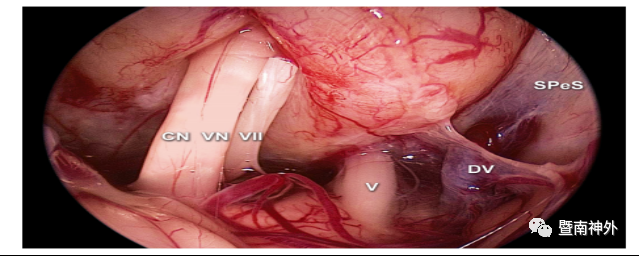

4.对于内听道前型CPA脑膜瘤,颅神经通常在肿瘤的后表面,需在颅神经的间隙中操作,并分块切除肿瘤。三叉神经是最能耐受推移的神经,需充分利用该神经上、下间隙作为手术通道,其他手术通道可选择CN VII/VIII复合体和后组颅神经之间的间隙。嵌入肿瘤内的颅神经和血管结构需小心保护,以免损伤;对于桥脑外侧缘需进行锐性分离,注意保护好桥脑腹侧表面的软脑膜及静脉,避免损伤脑干;

5.本例肿瘤长入’s囊腔、内听道口内,借助内镜或者反观镜小心分离其内与神经粘连紧密的肿瘤,避免损伤,实现了全切肿瘤及面、听神经功能保留的目标;